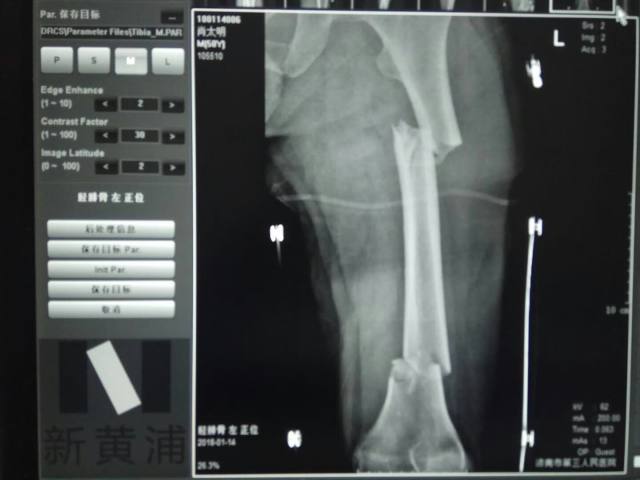

2018 年 2 月份,陈先生(化名)在车祸中受伤导致复杂股骨骨折,一根长骨断成几节,伤势严重,济南市第三人民医院创伤骨外一科主任谢新敏手术团队创新性地为其实施了「骨科机器人辅助下复杂股骨骨折闭合复位内固定术」,据查阅此例手术为山东省内首例。

图 1 复杂的股骨骨折